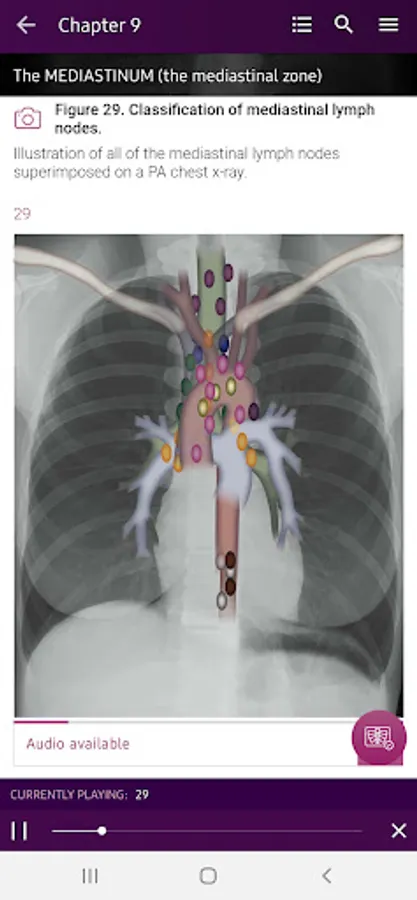

Section II* introduces the concept of radiological zones to give you a starting point in the understanding of the radiological anatomy of the chest. The next chapters review in detail the radiological anatomy of specific anatomical structures, also provide examples of how the x-ray image can change due to pathology. The final chapter explains how the individual structures come together to form the radiological image.